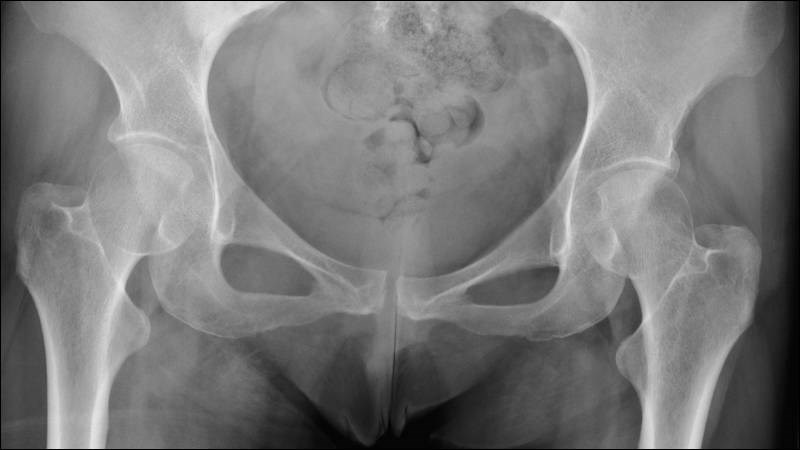

- Chụp X-quang.

-800x450.jpg)

Hình ảnh X-quang hỗ trợ chẩn đoán tình trạng đau hông